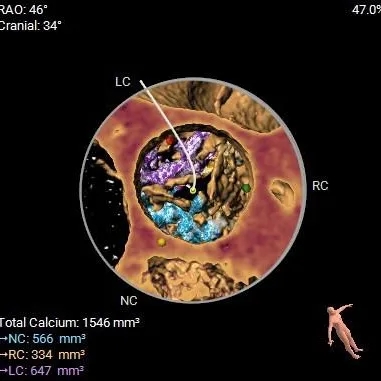

钙化积分测量达1546mm3

-

极重度钙化,左窦、无窦钙化较重